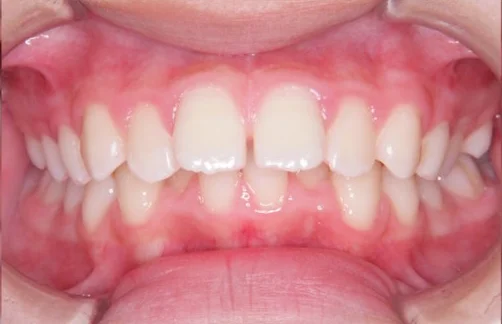

治療前

| 相談内容(主訴) | 前歯のガタガタが気になる |

|---|---|

| 診断結果/行った治療内容 | 叢生/アクティビティ+インビザライン矯正 |

| 治療期間/回数 | 1.5年/18回 |

| 治療費用 | 50万円(マイオブレイス+インビザライン)+アクティビティ 月一5,500円 |

| 治療のリスク/副作用 | 原則の装着時間を守らないと効果が出ません/まれに顎関節に症状が出ることがあります |